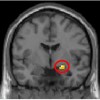

Brain Imaging Shows That A Sense Of Justice Is Built Into The Brain

A new study from Karolinska Institutet in Sweden shows that the brain has built-in mechanisms that trigger an automatic reaction to someone who refuses to share. The reaction derives from the amygdala, an older part of the brain. The subjects’ sense of justice was challenged in a two-player money-based fairness game, while their brain activity […]